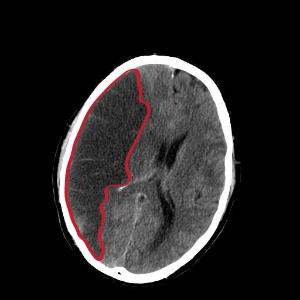

이번 포스팅에서 뇌경색 초기증상 모두 알아보려고 해요. 한 번쯤은 뇌경색, 뇌출혈, 뇌졸중에 대해서 들어보신 적이 있을꺼에요.

뇌경색 초기증상이 의심된다면 지금 바로 병원을 내방해 진단을 받고 적절한 치료를 손대는 것이 후유증을 감하는데 중요 해요. 시간이 관건이며, 뇌세포의 괴사, 증상 악화, 너무 늦으면 사망에 이를 수 있는 뇌혈관의 괴사를 피하기 위하여 증상이 나타난 뒤에 4시간 이내에 잘 맞은 약물, 시술 또는 수술을 신속히 실시해야 합니다. 치료로 즉시 하셔야 해요.